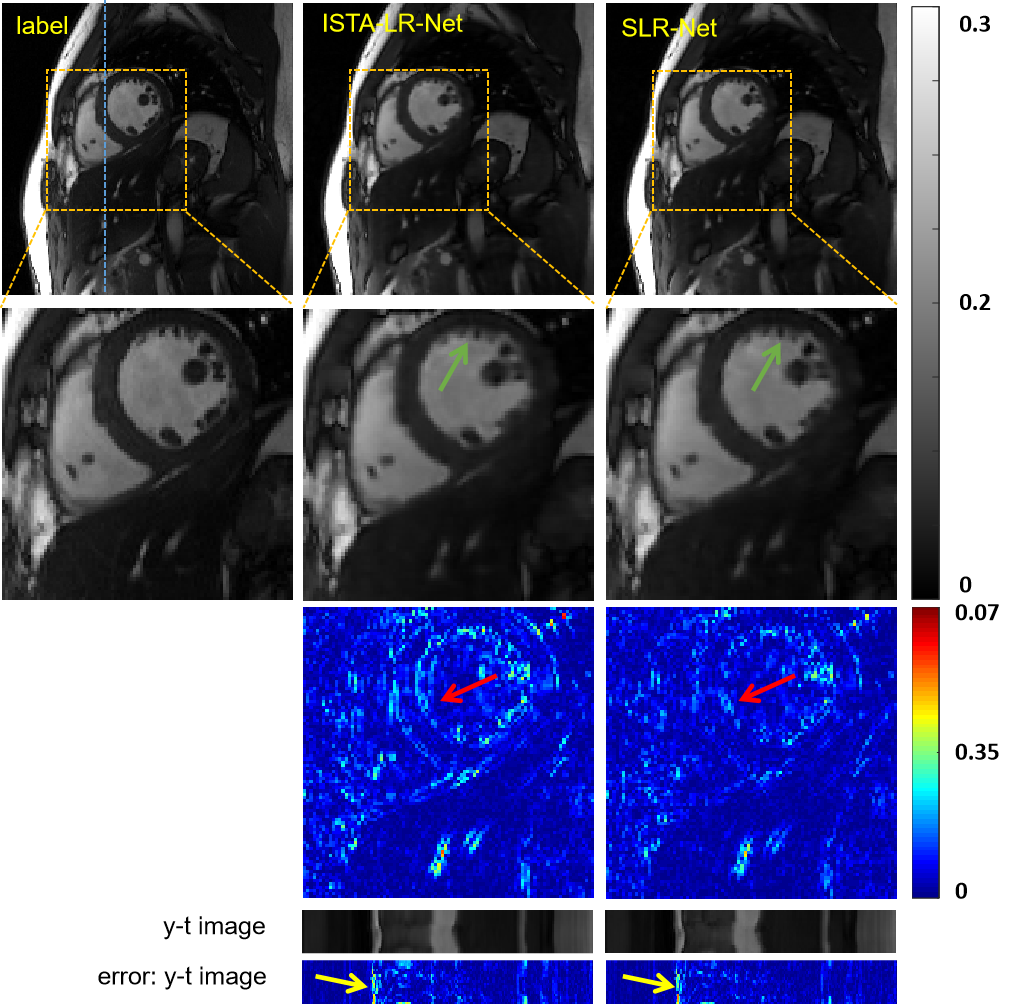

IV-B Which of the Two Schemes Performs Better

The above sections demonstrate that both schemes that introduce deep low-rank prior can lead to improvements in the reconstructed results. In this section, we will explore which of these two schemes works better. To be fair, the same baseline is needed, and we regarded ISTA-Net as the baseline method. Obviously, SLR-Net is the unrolling version of deep low-rank prior based on ISTA-Net. Its plug-and-play version of deep low-rank prior is ISTA-LR-Net as shown in Fig.2 (d). The reconstruction results of these two models at 8-fold acceleration are shown in Fig.7. Both models have achieved better reconstruction performance, but SLR-Net has some advantages in preserving detail, as shown by the green arrow. SLR-Net also has certain progress in quantitative indicators, as shown in Table IV. Therefore, we come to the conclusion that under the same baseline, unrolled deep low-rank prior is superior to plug-and-play deep low-rank prior. We conjecture that the main reason is that in the plug-and-play scheme, a first-order Taylor expansion (Eq.17) is used to approximate the regularizer , which is a relaxed approximation due to its nonsmoothness, while in the unrolling scheme, the regularizer is exactly used (Eq.13).

Both schemes have their own advantages and applicable scenarios: Unrolled deep low-rank prior requires a highly customized optimization model and solution algorithm. If all of these are available, we recommend using the first schemes to get the best reconstruction results. The highlight of plug-and-play deep low-rank prior is its portability. If it is non-trivial to build an unrolled SLR network in other imaging systems, plug-and-play deep low-rank prior is recommended to utilize the low-rank prior quickly.